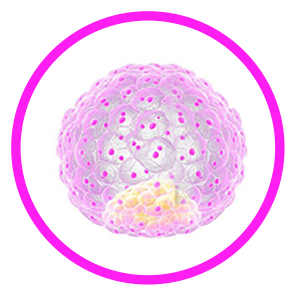

The full form of IVF is In Vitro Fertilization which means the fertilization is carried outside the body. Insemination which means meeting of sperm and the egg is done in a petri dish of a laboratory. For this procedure, eggs from the female are retrieved and at the same time sperms from the male partner are collected. After fertilization of the egg and sperm, the embryo is formed which is transferred in the womb of the female.